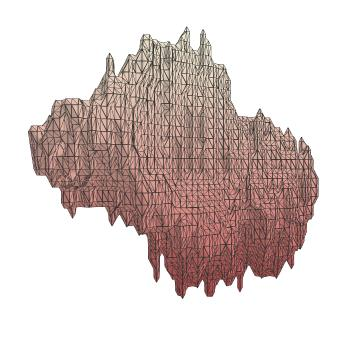

The human annotations are imperfect, especially when produced by junior practitioners. Multi-expert consensus is usually regarded as golden standard, while this annotation protocol is too expensive to implement in many real-world projects. In this study, we propose a method to refine human annotation, named Neural Annotation Refinement (NeAR). It is based on a learnable implicit function, which decodes a latent vector into represented shape. By integrating the appearance as an input of implicit functions, the appearance-aware NeAR fixes the annotation artefacts. Our method is demonstrated on the application of adrenal gland analysis. We first show that the NeAR can repair distorted golden standards on a public adrenal gland segmentation dataset. Besides, we develop a new Adrenal gLand ANalysis (ALAN) dataset with the proposed NeAR, where each case consists of a 3D shape of adrenal gland and its diagnosis label (normal vs. abnormal) assigned by experts. We show that models trained on the shapes repaired by the NeAR can diagnose adrenal glands better than the original ones. The ALAN dataset will be open-source, with 1,594 shapes for adrenal gland diagnosis, which serves as a new benchmark for medical shape analysis. Code and dataset are available at https://github.com/M3DV/NeAR.